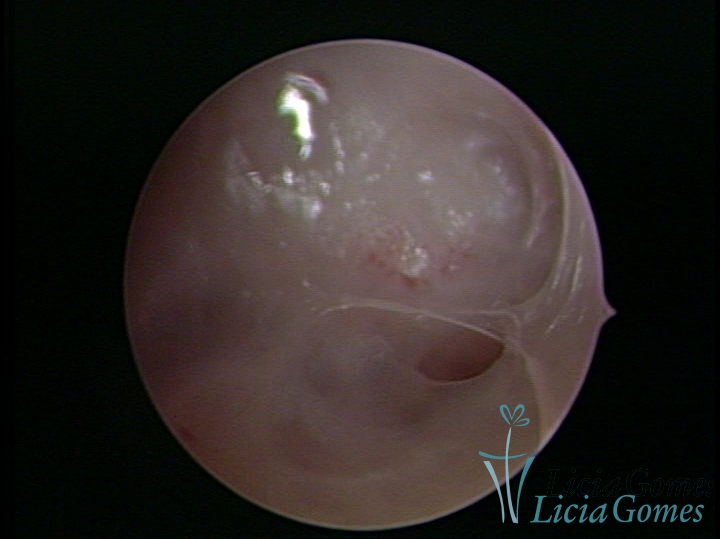

Sinéquia TIPO FIBROSA

• SINÉQUIA TIPO FIBROSA